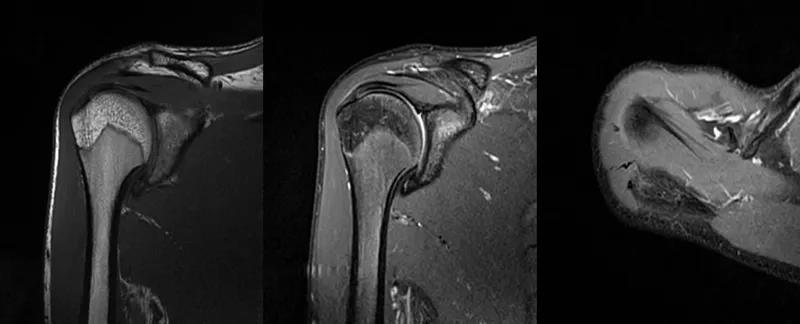

2、MRI检查MRI目前是诊断肩袖疾病中最常用的检查,可以直观的观察肩袖肌腱。

图24 a.肩袖全层撕裂;b.正常MRI

图25 巨大肩袖损伤(冈上肌)